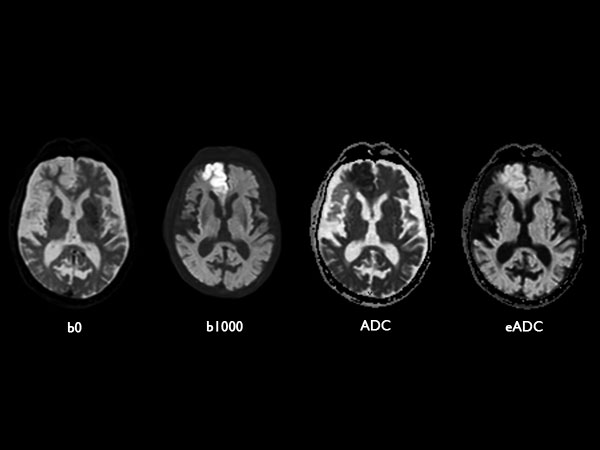

Acute stroke. Patient was brought to the first aid and directly transferred to the MRI unit. Axial studies were performed to get an overview of the stroke. Total study time is 9 minutes.

Diffusion